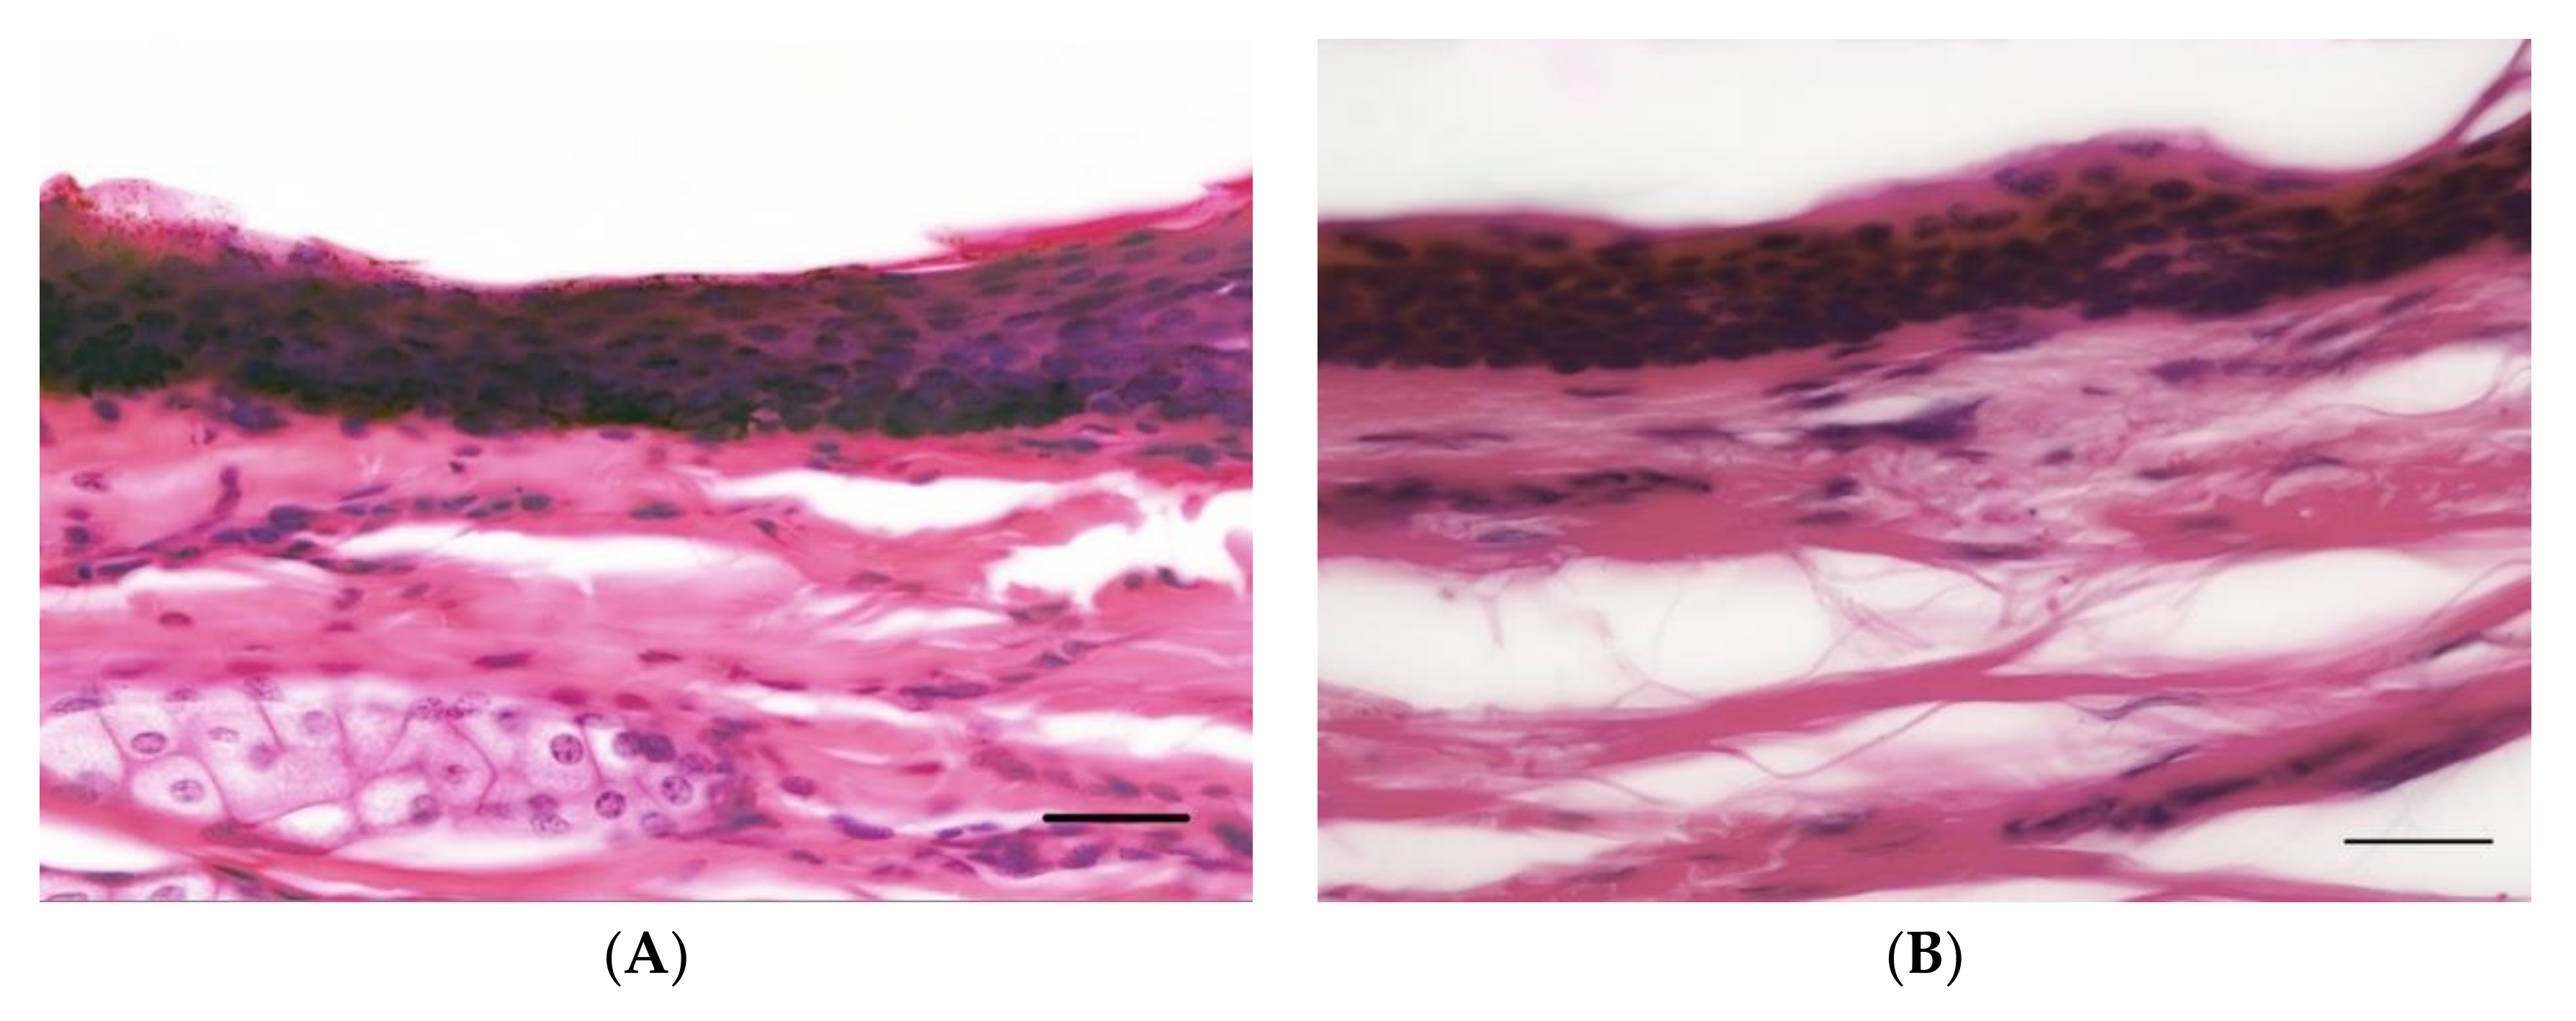

马(A)和人(B)皮肤切面的染色图(第二张图红色为神经末梢):

Tong L, Stewart M, Johnson I, et al. A comparative neuro-histological assessment of gluteal skin thickness and cutaneous nociceptor distribution in horses and humans[J]. Animals, 2020, 10(11): 2094.